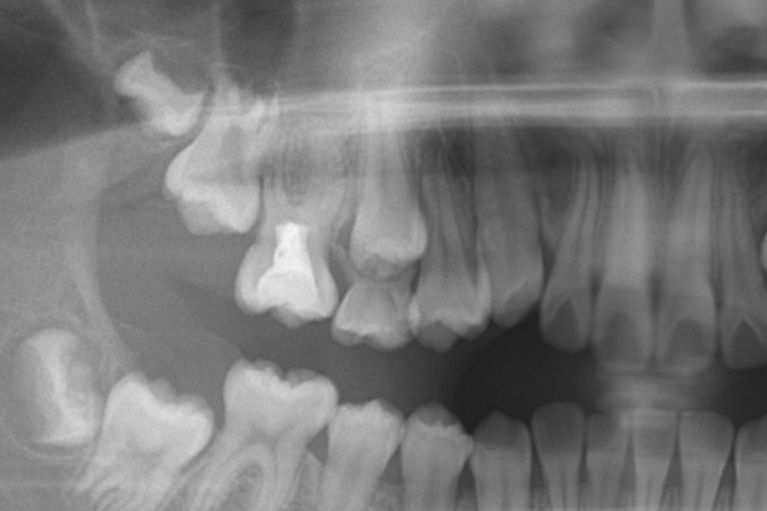

術前

術中

術後

| 治療名 | ダイレクトボンディング・セラミックインレー |

|---|---|

| 治療説明 | 以前他院で行ったハイブリッドセラミックインレーが劣化したためセラミックインレーとダイレクトボンディングで再修復を行いました。 |

| 治療回数・期間 | 2回 |

| 副作用とリスク | 一時的に知覚過敏が生じることがあります。セラミックとレジンが破折し、再修復が必要になる可能性があります。 |

| 料金(税込) | セラミックインレー:77,000円 ダイレクトボンディング:55,000円 合計:132,000円 |